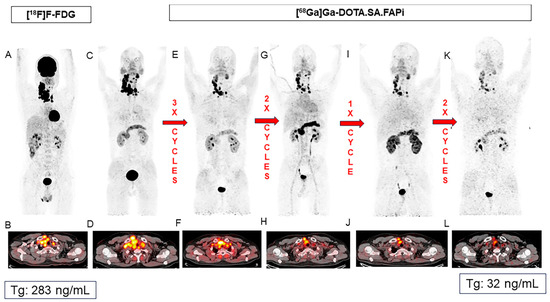

- Ballal, S.; Yadav, M.P.; Moon, E.S.; Roesch, F.; Kumari, S.; Agarwal, S.; Tripathi, M.; Sahoo, R.K.; Mangu, B.S.; Tupalli, A.; et al. Novel Fibroblast Activation Protein Inhibitor-Based Targeted Theranostics for Radioiodine-Refractory Differentiated Thyroid Cancer Patients: A Pilot Study. Thyroid 2022, 32, 65–77. [Google Scholar] [CrossRef] [PubMed]

- Ballal, S.; Yadav, M.P.; Satapathy, S.; Roesch, F.; Chandekar, K.R.; Martin, M.; Shakir, M.; Agarwal, S.; Rastogi, S.; Moon, E.S.; et al. Long-Term Outcomes in Radioiodine-Resistant Follicular Cell-Derived Thyroid Cancers Treated with [177Lu]Lu-DOTAGA.FAPi Dimer Therapy. Thyroid. 2025, 35, 188–198. [Google Scholar] [CrossRef] [PubMed]

| Ballal et al. [51] | 2022 | 15 | 57 (39–67) | 4/11 | [177Lu]Lu-DOTAGA.(SA.FAPi)2 | Radioiodine-refractory metastasized thyroid cancer |

| Ballal et al. [52] | 2025 | 73 | Mean age 54.3 (27–80) | 36/37 | [177Lu]Lu-DOTAGA.(SA.FAPi)2 (n = 65) and [177Lu]Lu- and [225Ac]Ac-DOTAGA.FAPI dimers (n = 8) | Radioiodine-resistant follicular cell-derived thyroid cancers |

| Ballal et al. (2022) [51] | 7.4 months | 3 | Tumor lesions: 10.8 | VAS and GPA response criteria: 23% (3/13) complete response, 38.4% (5/13) partial response, 30.7 (4/13) minimal response, 7.7% (1/13) no response. | NR | NR | NR |

| Ballal et al. (2025) [52] | 3 years | 4 | NR | NR | NR | PR: 18/36 (50%) 4 SD: 9/36 (25%) 4 PD: 9/36 (25%) 4 | 29 (32) |

| [177Lu]Lu-DOTAGA.(SA.FAPi)2 | Dimeric FAP ligand | Significantly longer tumor retention and higher tumor dose than DOTA.SA.FAPi; durable uptake across cycles | Median absorbed dose in tumor lesions: 6.70 in initial series; up to 10.8 Gy/GBq in thyroid cancer cohort | Ballal et al. [21,50,51,52] |